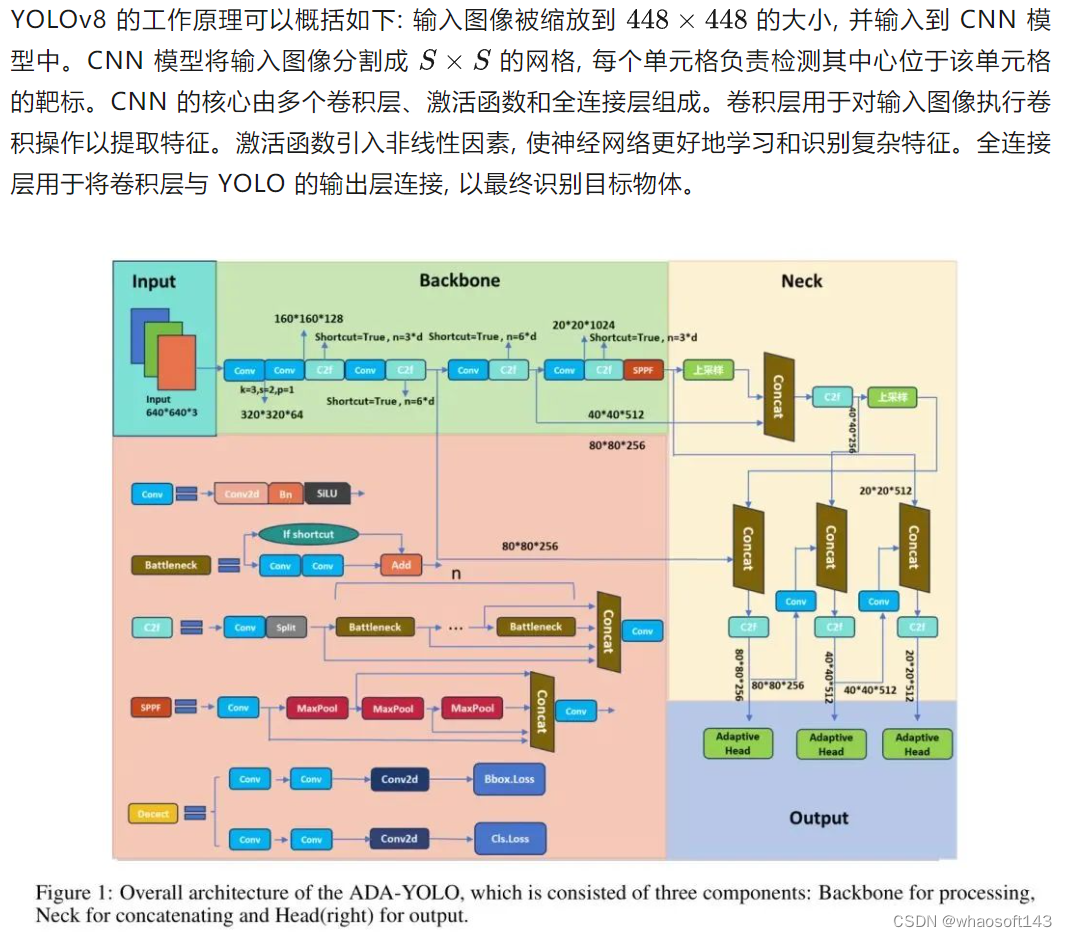

2.0 ADA-YOLO

一种内存高效的 ADA-YOLO 模型,该模型利用新颖的架构和训练策略来增强医学图像中多目标检测的鲁棒性。通过在各种数据集上的实验,证明了 ADA-YOLO 在处理医学图像中的遮挡相关挑战方面具有优越性能。模型在准确局部化和分类多个目标方面,即使在遮挡条件下也表现出卓越性能。YOLOv8+注意力+Adaptive Head,相对YOLOv8,mAP提升3%+118FPS

为了解决这个问题,作者提出了一种名为ADA-YOLO的轻量级但有效的医学目标检测方法,该方法将注意力机制与YOLOv8架构相结合。作者提出的这种方法通过自适应头模块利用动态特征定位和并行回归进行计算机视觉任务。

简而言之,本文的主要贡献如下:

- 提出了一个轻量级但强大的目标检测模型,称为ADA-YOLO,其有效性已经通过实证实验得到证明,该模型在 mAP(平均平均精确率)方面可以超过 YOLOv8,同时还能在精确度和召回率指标之间实现惊人的平衡;同时,在训练过程中,该模型具有内存效率,这展示了其在便携式场景和云边协作中的巨大潜力。

- 深入研究了 YOLOv8 架构的复杂性,并设计了一个高效的目标检测组件,称为 自适应头(AH),它结合了 动态视觉特征定位(DVF)和 联合引导回归模块(JGR),使得边界框回归和分类预测可以并行计算,从而实现更精确的物体定位,进而提高检测精度,同时由于并行机制,实现了更好的计算效率。

Yolov8 Model

2.2.1 Model Architecture

YOLOv8

Backbone。 YOLOv8 中的 Backbone 网络充当特征提取器,通常使用卷积神经网络(CNN)架构,如 Darknet、CSPDarknet 或 CSPDarknet-tiny 等。它的主要功能是从输入图像中提取特征,这些特征用于后续的任务,如目标检测。

通过一系列卷积和池化操作, Backbone 网络逐步减少特征图的空间维度,同时增加这些特征图的深度。这个过程旨在捕捉不同层次的特征,有效允许神经网络捕捉和表示输入图像中不同复杂性和尺度的特征。

Neck。颈是一个可选组件,用于进一步处理 Backbone 网络提取的特征图。其主要目的是集成不同层次的特征信息,以提高目标检测的性能。通常,颈包括各种操作,如卷积、上采样和下采样,旨在合并具有不同分辨率的特征图。这种集成是为了提高网络捕捉目标物体上下文和详细信息的能力。

Head。在目标检测任务中,头是一个关键组件,负责生成边界框、分类概率和目标属性。头通常由卷积层和全连接层组成,用于从特征图中提取与检测到的物体位置和分类标签相关的信息。生成的边界框可能需要经过后处理步骤,如非极大值抑制,以获得最终的目标检测结果。

YOLOv8 Object Detection Algorithm

图3显示了 YOLOv8 的详细架构。YOLOv8 采用了与前一个模型 YOLOv5 类似的 Backbone 网络,但在 CSPLayer(现在称为 C2f 模块)方面取得了显著改进。这个模块的主要目标是通过融合高层次特征和上下文信息来提高检测精度。YOLOv8 框架使用单个神经网络同时预测边界框和分类概率,简化了目标检测过程。与基于 Anchor 点的机制和特征金字塔网络相结合,YOLOv8 特别擅长在不同尺度下检测目标。

YOLOv8 在医学目标检测中的工作流程包括几个关键步骤。首先,将输入的医学图像进行预处理,以确保与 YOLOv8 模型兼容。然后,图像经过神经网络,其中特征提取和目标检测以统一的方式进行。YOLOv8 将输入图像分成网格,并分配每个网格单元的边界框,预测目标类别和置信度分数。值得注意的是,使用多个 Anchor 框增强了模型准确定位和分类不同大小物体的能力。

Adaptive Head

作者提出了一种基于 YOLOv8 的有效架构,该架构通过一个可适应的 Head 进行微调,该 Head 针对下游任务进行自适应。在标准的计算机视觉任务中, Head 将问题建模为基于 Anchor 点的预测。

具体而言,检测模型使用 Anchor 框,这些 Anchor 框是不同大小和长宽比预定义的边界框。通过预测这些 Anchor 框的偏移量和缩放因子, Head 能够准确地定位各种大小和形状的物体。在实际场景中,这种特性由于输入尺寸的多样性和随机性,可能比简单的检测方法更具有优势。例如,当输入尺寸多样且随机时,非自适应的检测方法可能需要数十次图像预处理或超参数调整才能适应输入。

相反,作者的方法可以自动地根据输入形状动态生成 Anchor 框,称为动态视觉特征定位。这使得模型能够适应不同的输入分辨率和长宽比,使其在检测不同场景下的物体时更加通用和鲁棒。与 [27] 不同,作者删除了激活层,以保留更多的信息在中间张量中,以更好地完全捕捉传递语义,同时提高了一定的计算效率。

同样重要的是,由于预定义的边界框属性,检测问题被简化为一个简单的回归问题,即关于尺度和偏移量的回归。动态 Anchor 框设置使得模型能够挖掘图像中存在的细粒度信息。该架构也利用动态视觉特征定位(DVF)模块来提高训练稳定性和收敛速度,如图所示。DVF模块对预测的边界框坐标进行自适应正则化,使模型能够学习为不同物体大小适当调整预测框的大小。